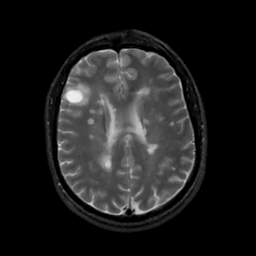

MR Study #6, March 17, 1991 -- Slice #32

[Home][Help][Clinical][Tour 1][Tour 2] Slice 32